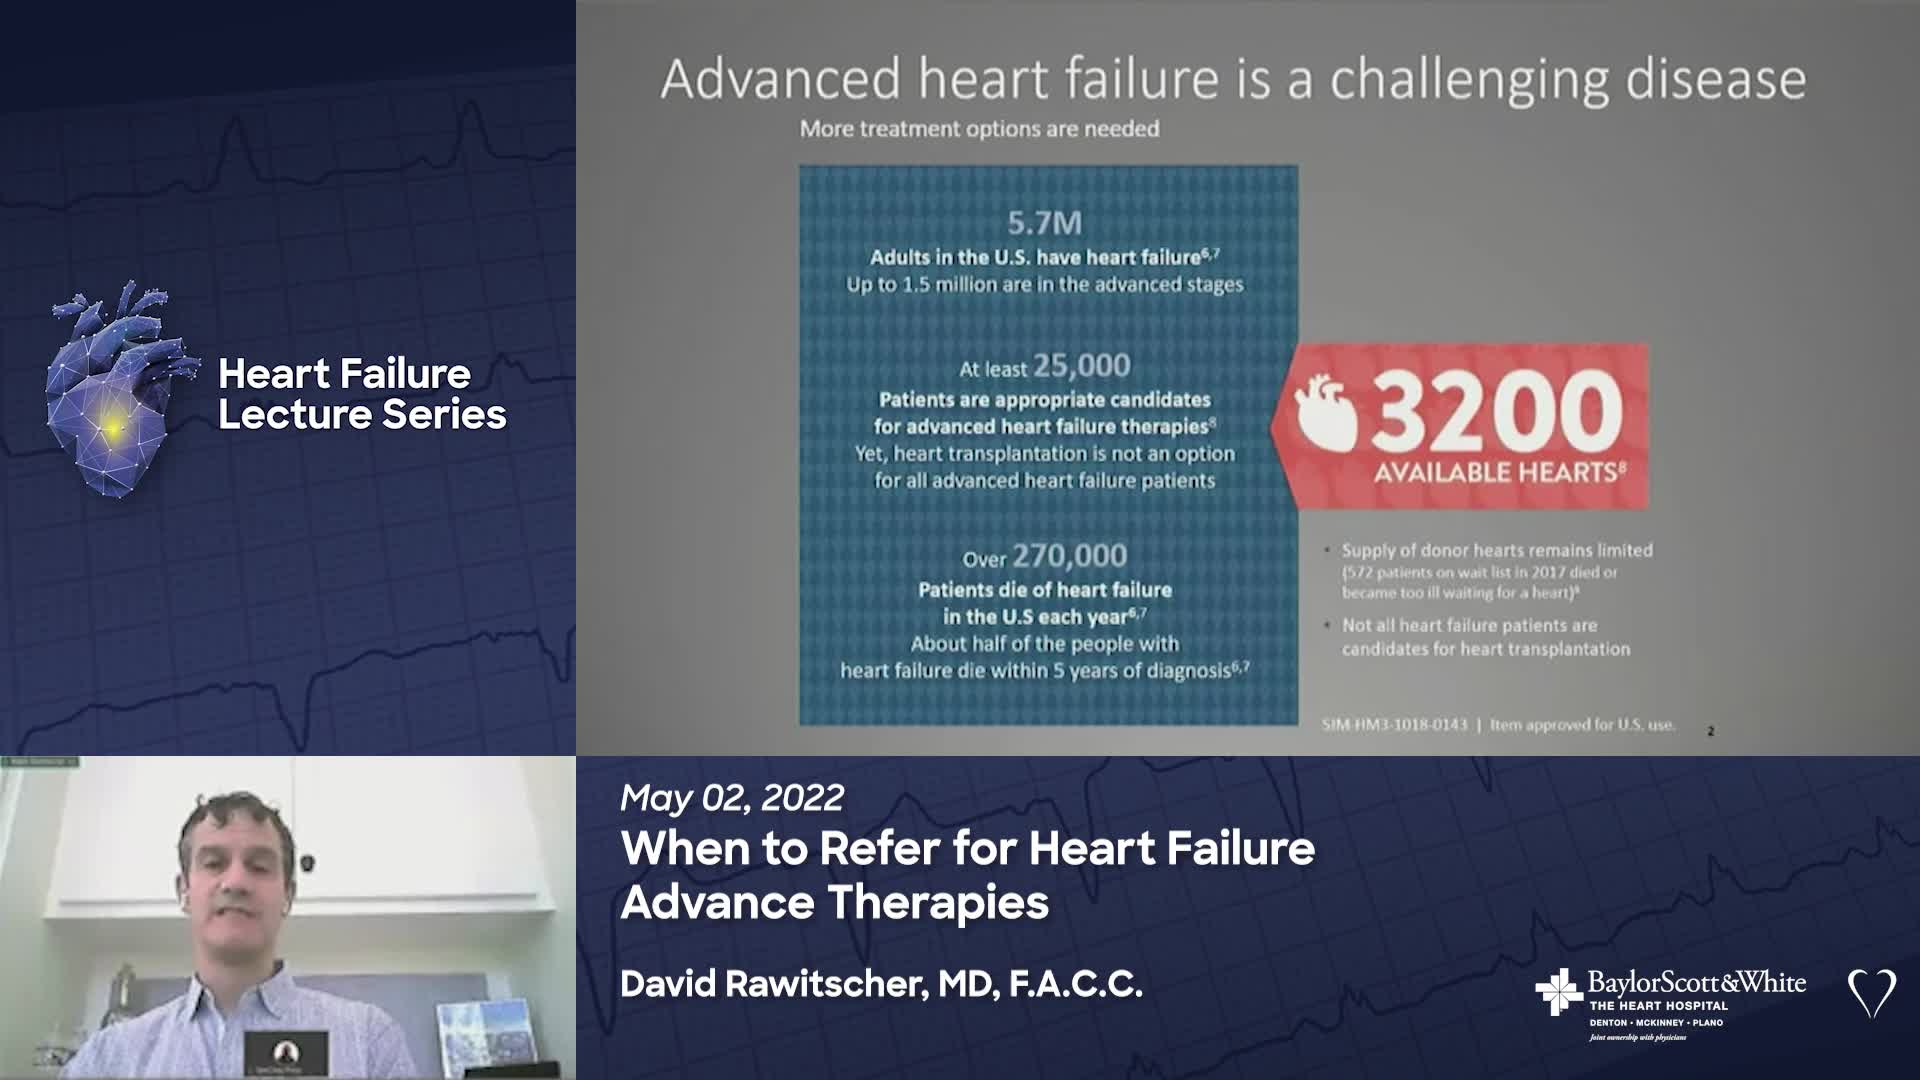

FACET

Our mission is to provide a collaborative environment and educational opportunities for physicians, scientists, nurses, and medical professionals to discuss and teach advanced techniques, improve clinical knowledge, and enhance the ability to provide excellent patient care, which ultimately improves patient health outcomes. To that end, the education program has strived to meet this goal educating and training the local, regional, and national medical community on the most recent advancements in medical science and research.

FACET CARDIOVASCULAR

FACET CARDIOVASCULAR